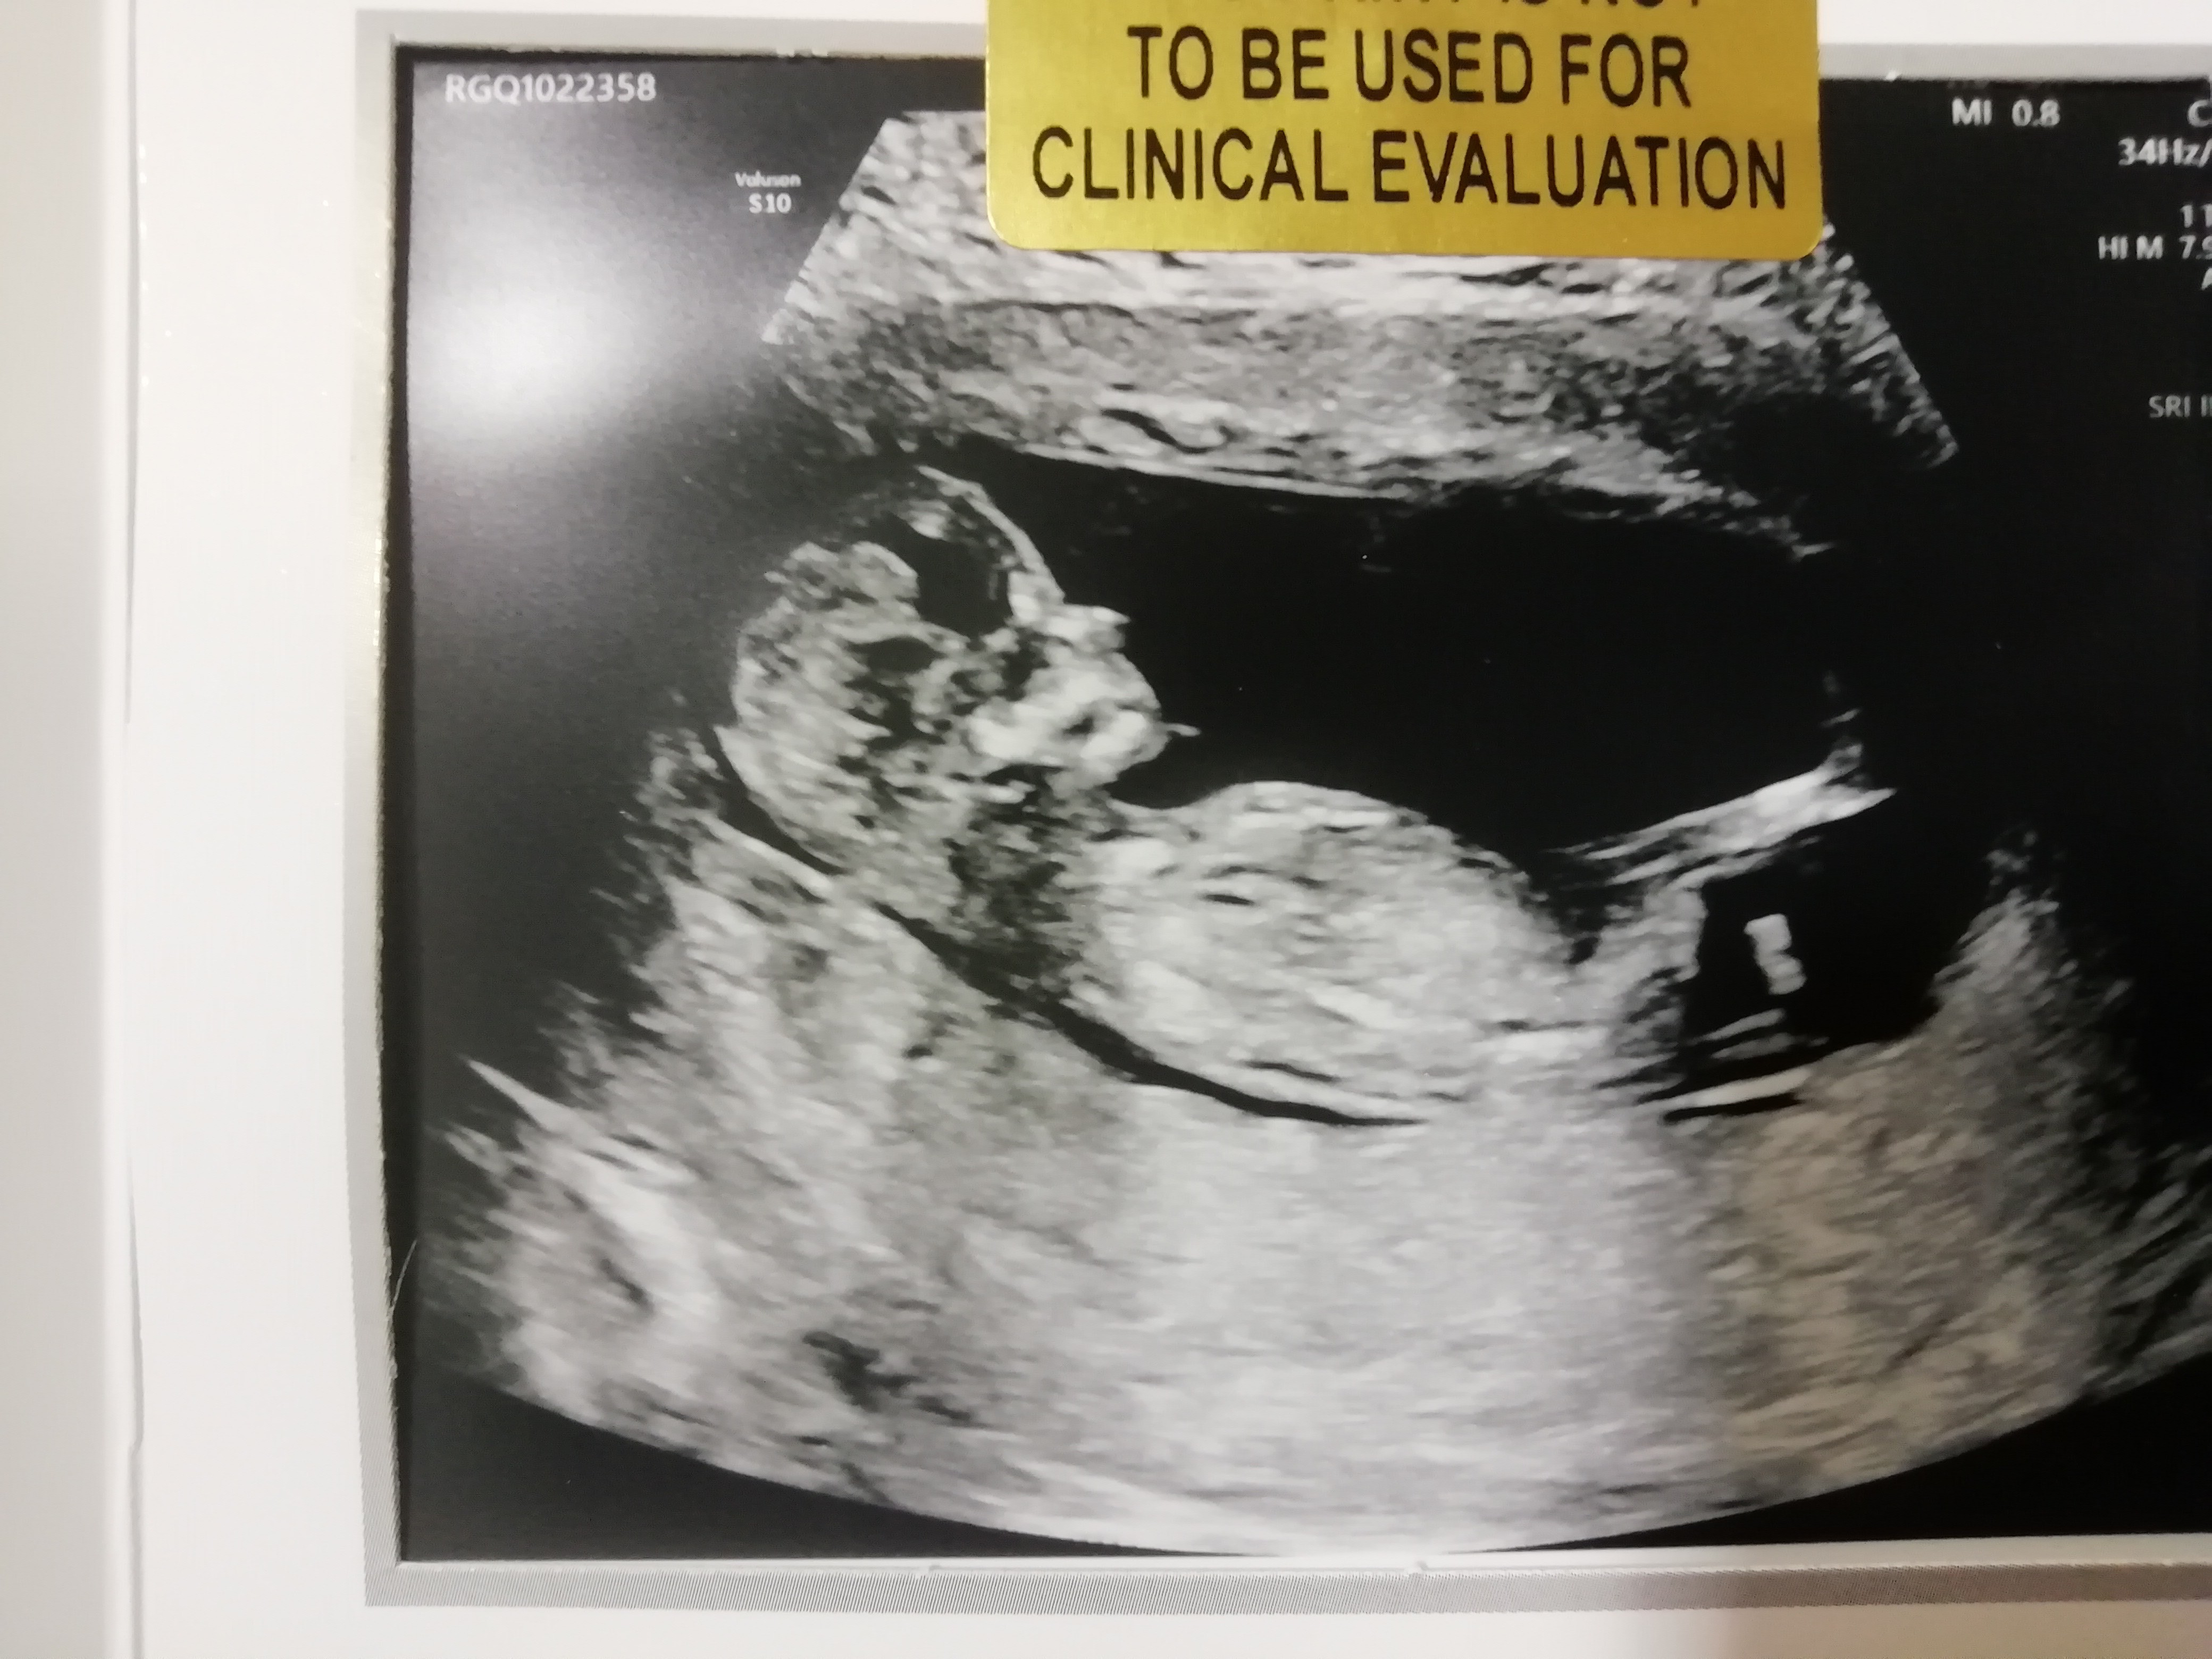

Ja po prenatalnych, wszystko ok, bejbik skakal ☺️ przeziernosc 1.7 12+4

• IMG_20191114_162832.jpg

IMG_20191114_162832.jpg

1,4 MB · Wyświetleń: 129